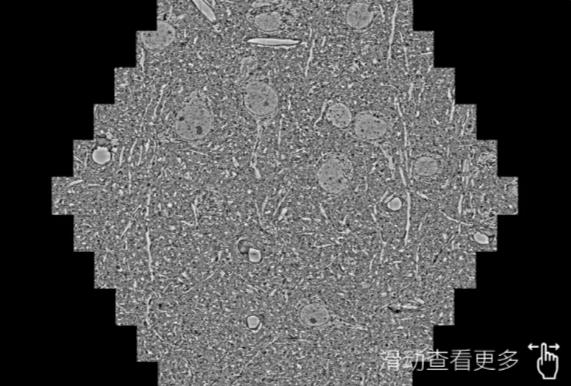

鼠脑切片。左图使用河池蔡司河池扫描电镜MultiSEM706对165μmx143pm面积区域成像,耗时仅需1.5秒。右图为鼠脑切片中30μm区域放大效果。样品由芝加哥大学B.Kasthuri提供。

使用蔡司高速河池扫描电镜MultiSEM对1mm²人脑皮层组织进行高分辨成像,并对其中的各种细胞结构进行三维重构分析。左图展示了2x3mm²组织平面中锥体神经元的三维重构效果。右图显示了局部体积神经元三维重构。图像由哈佛大学chtman实验室提供,渲染图由D. Berger 制作。